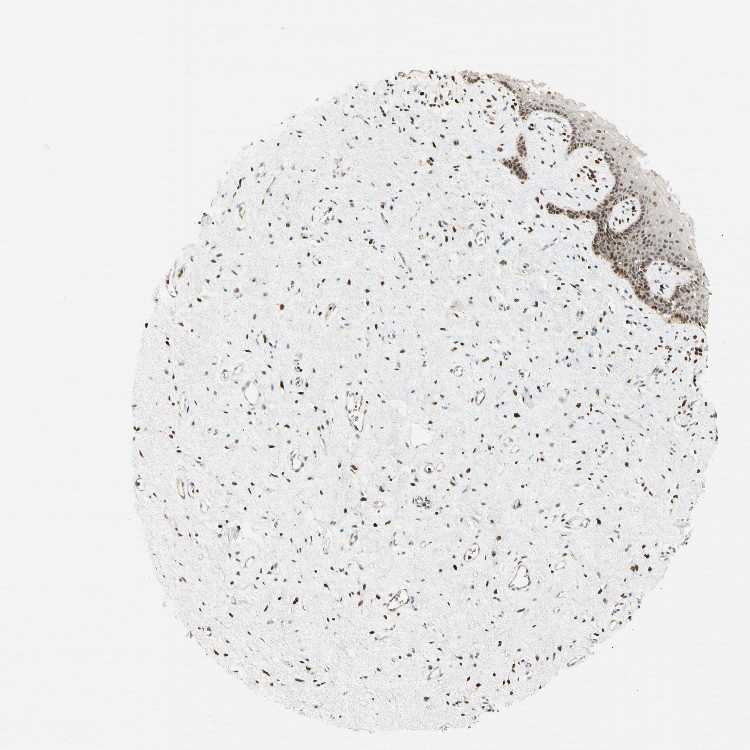

TISSUE PRIMARY DATA VAGINA Show tissue menu

VAGINA - Antibody stainingi

Antibody staining in the annotated cell types in the current human tissue is reported as not detected, low, medium, or high, based on conventional immunohistochemistry profiling in selected tissues. This score is based on the combination of the staining intensity and fraction of stained cells.

Each image is clickable and will lead to virtual microscopy that enables deeper exploration of all samples and also displays staining intensity scores, fraction scores and subcellular localization as well as patient and tissue information for each sample.

Antibody HPA050779Antibody CAB009250

Squamous epithelial cells MediumLow